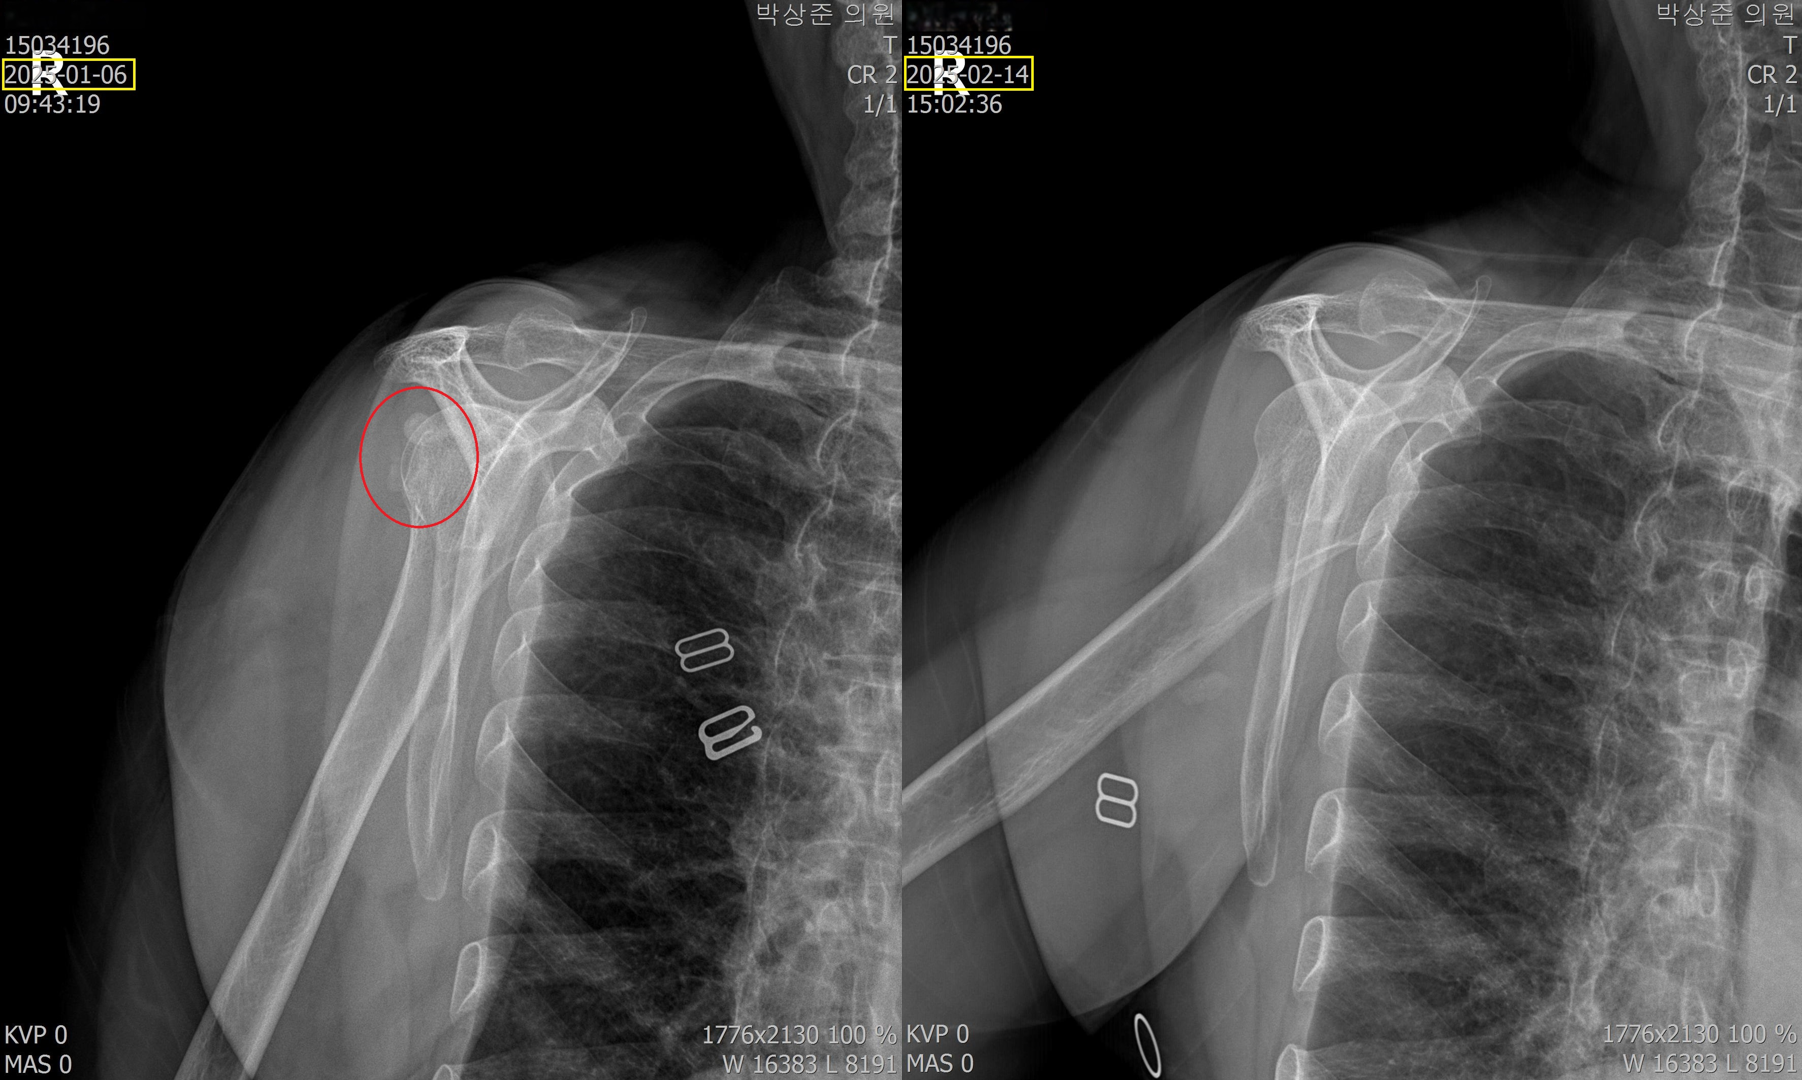

이렇게 5회 정도를 제거하고 찍은 비포 & 애프터 사진입니다. 최초의 빨간 동그라미 안의 석회가 거의 다 사라지고 약간 뿌연 정도로만 남아있는걸 확인할 수 있습니다. 이분은 이 치료 후 통증이 90% 가량 호전되었고 남은 통증은 시간이 지나면서 서서히 줄어들어서 지금은 통증이 거의 없는 상태로 지내고있습니다.